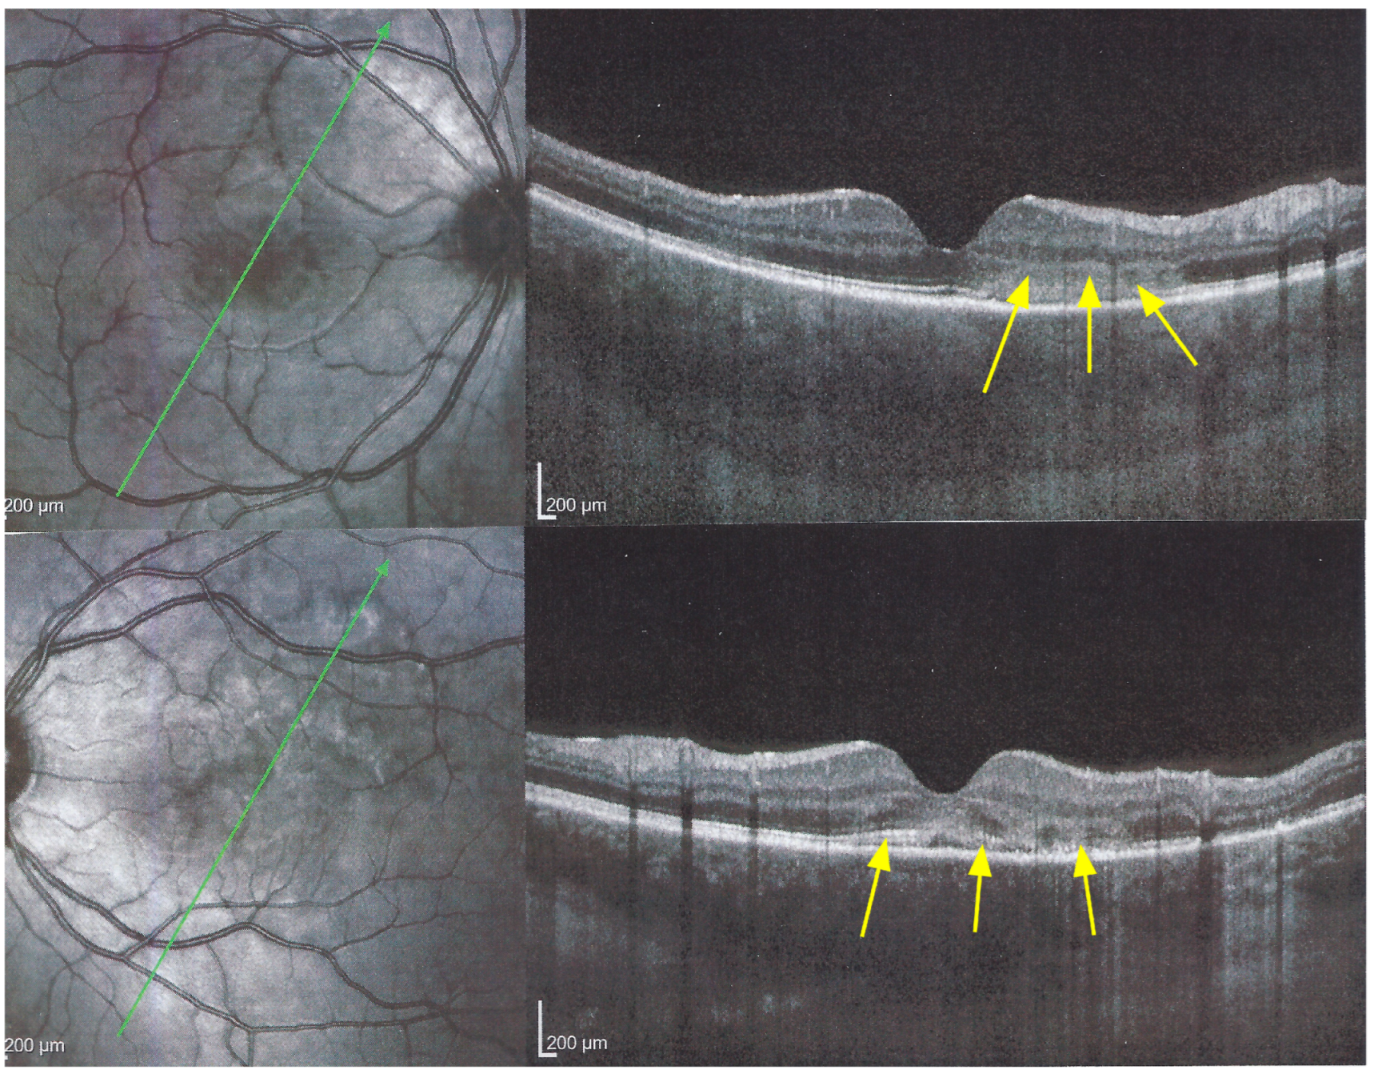

Figure 8. APMPPE/AMIC; SD-OCT in initial-acute phase OD (top) and OS (bottom) (same patient as Figure 5, Figure 6 and Figure 7a). In this initial phase, SD-OCT shows areas of hyperreflective changes visible in the outer plexiform layer and adjacent outer nuclear layer (arrows) but no loss of photoreceptor outer segments (see Figure 5).

The chorioretinal findings by spectral domain optical coherence tomography (SD-OCT) depend on the degree of involvement and the stage of the disease [5,7,25]. In early-acute disease ischaemia, induced by choriocapillaris non-perfusion, causes thickening of the outer retina including the IS/OS line and beyond (Figure 8). In later stages, SD-OCT can show either simple loss of photoreceptor outer segments, thickened RPE or atrophy with loss of RPE (Figure 9).

SD-OCT findings included thickened hyperreflective areas of the outer retina in the very early disease phase (10/35 eyes) (Figure 8 and Figure 11), photoreceptor outer segment loss and/or ellipsoid zone disruption-RPE alterations (22/35 eyes) (Figure 9), subretinal fluid (serous retinal detachment—SRD) (4/35 eyes), (Figure 14) and atrophy (3/35 eyes) in the late stage of the disease (Figure 15).